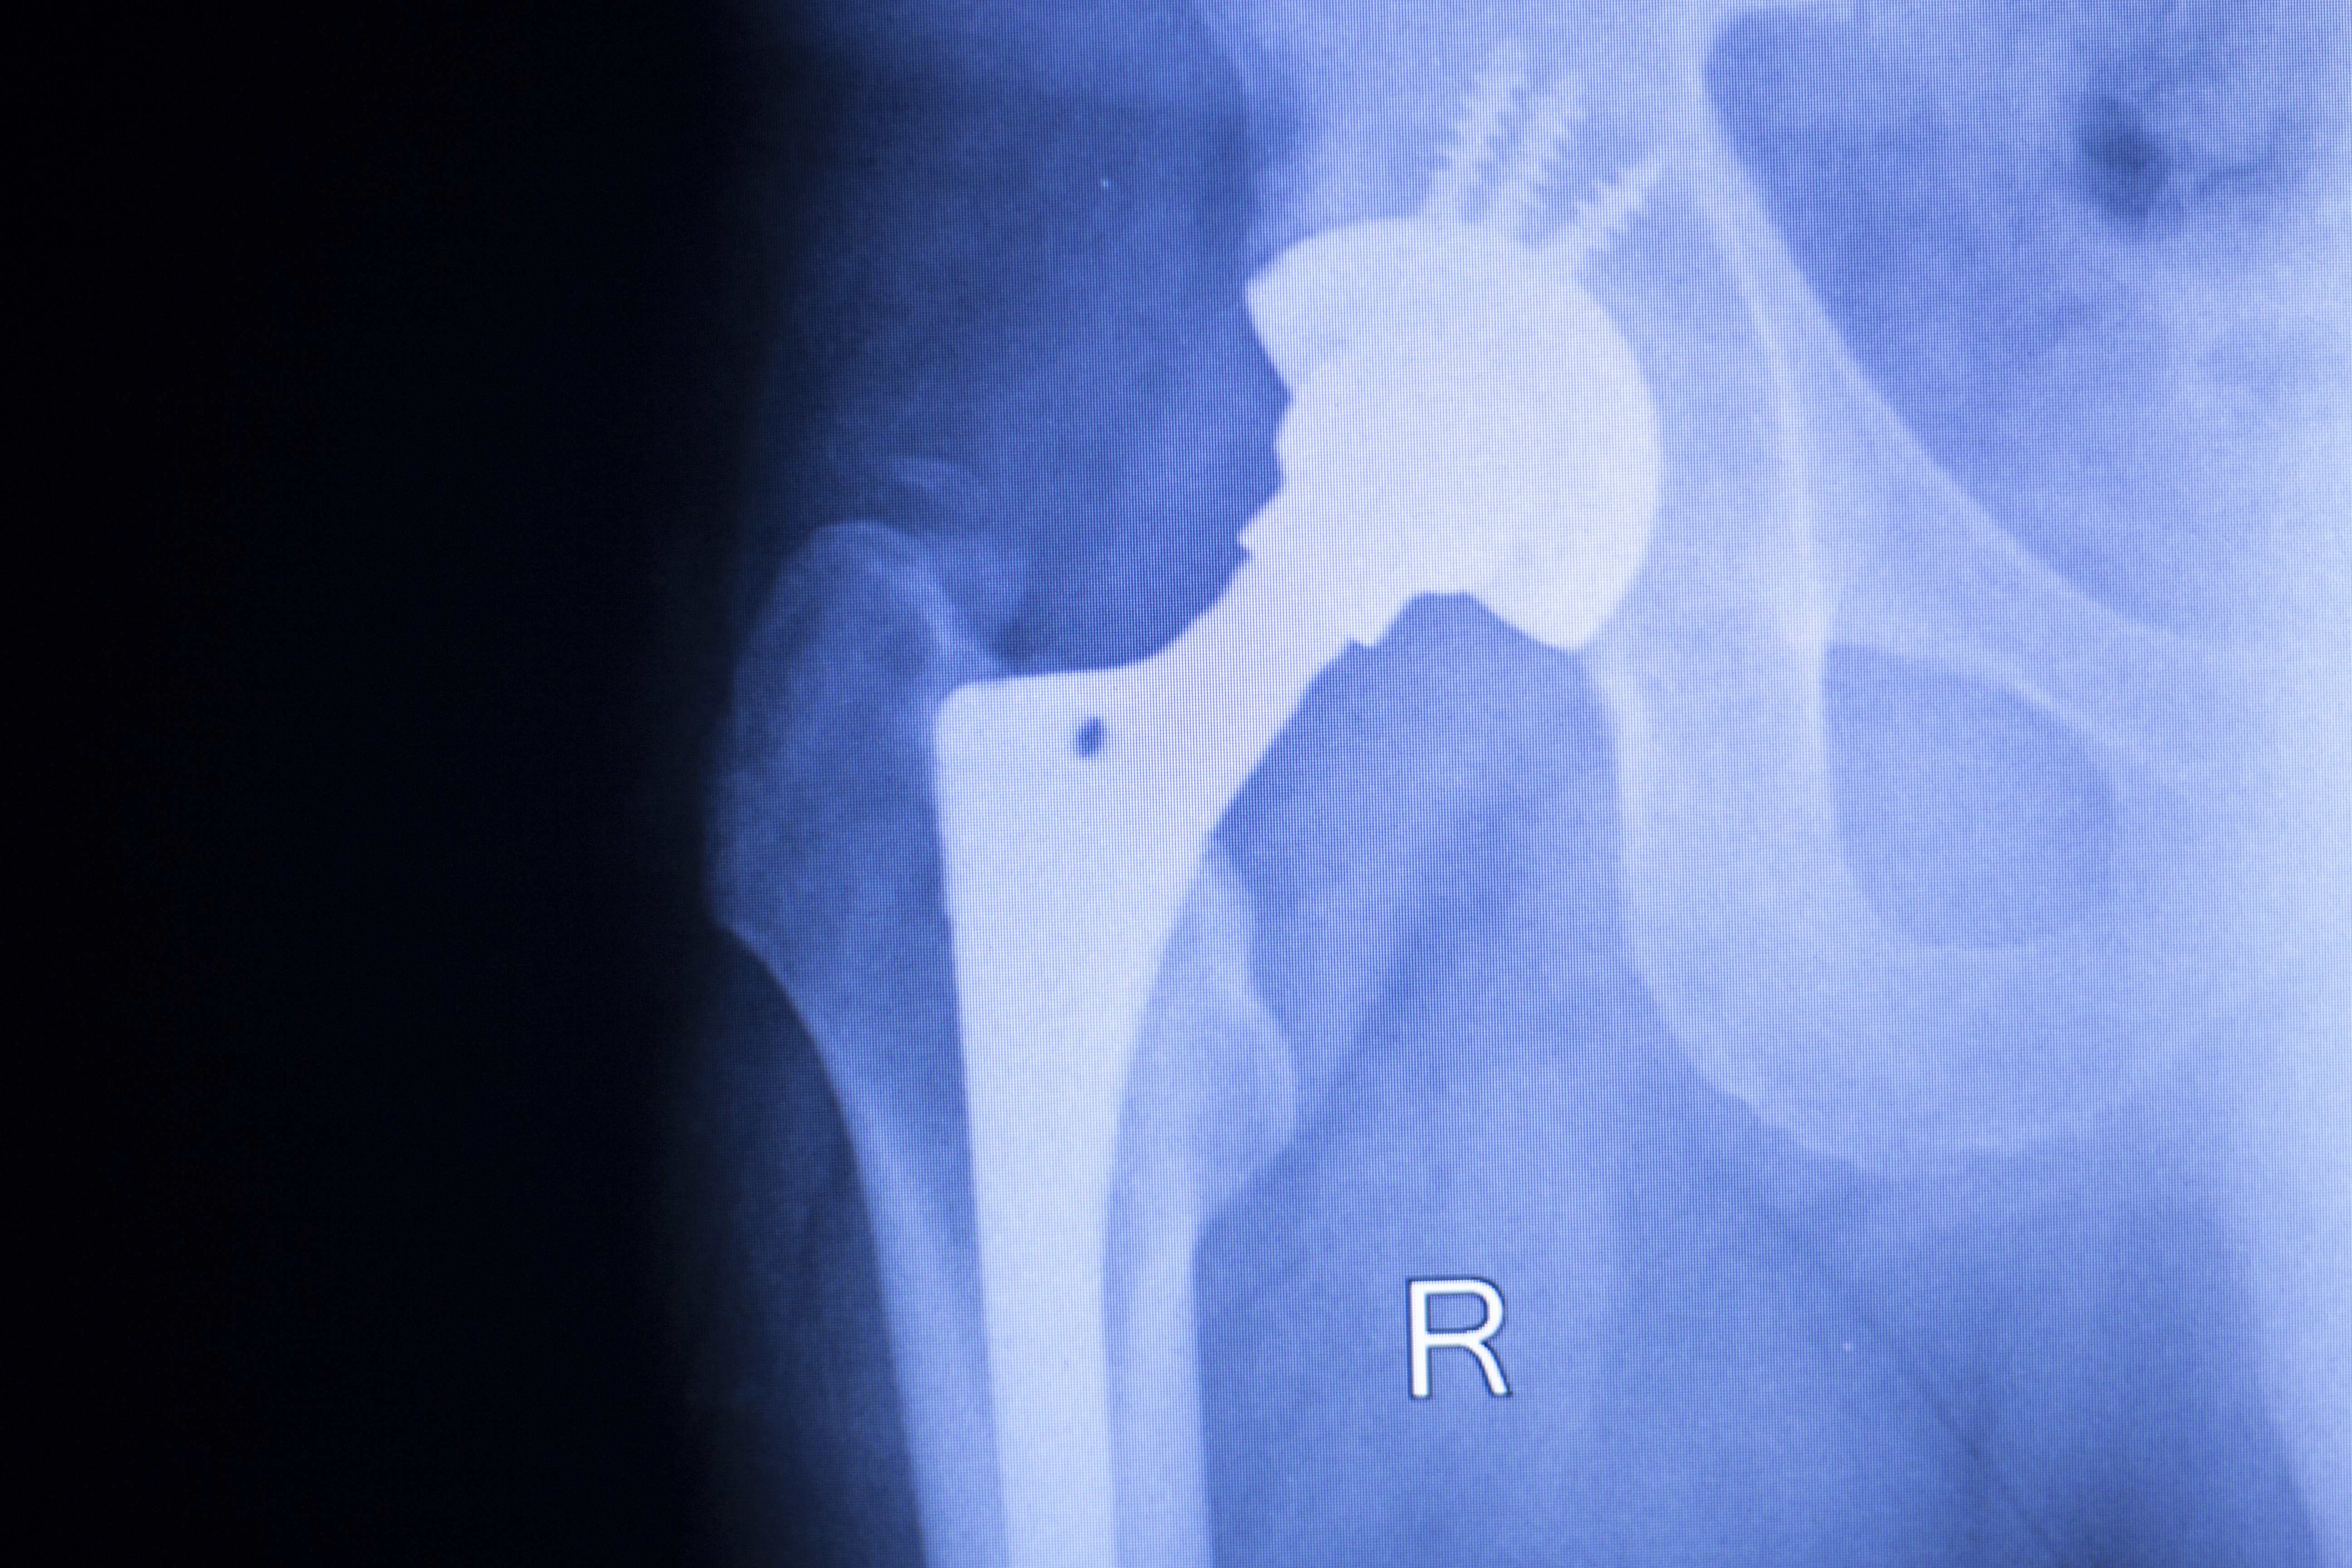

Eldre pasienter ble spart for påkjenningen av å måtte opereres på nytt da flere kirurger over hele landet gikk over til sementerte lårbenstammer i hofteproteseoperasjoner.

Særlig kvinner over 75 år og pasienter med hoftebrudd har nytte av at kirurgene går bort fra å bruke usementerte lårbenstammer til heller å benytte sementerte lårbenstammer i hofteproteseoperasjoner.

— Prosjektet ble satt i gang fordi vi observerte en økende bruk av usementerte lårbenstammer i Norge. Dette til tross for at alle nyere studier viser at risikoen for reoperasjoner er høyere dersom disse stammene brukes, enn dersom en bruker sementerte stammer. Risikoen er spesielt høy for å pådra seg brudd rundt proteser, hvilket medfører store reoperasjoner. Særlig høy er risikoen for de eldste pasientene, og spesielt for kvinner over 75 år og for pasienter med hoftebrudd, sier Jan-Erik Gjertsen.

Foto: Jan Erik Gjertsen